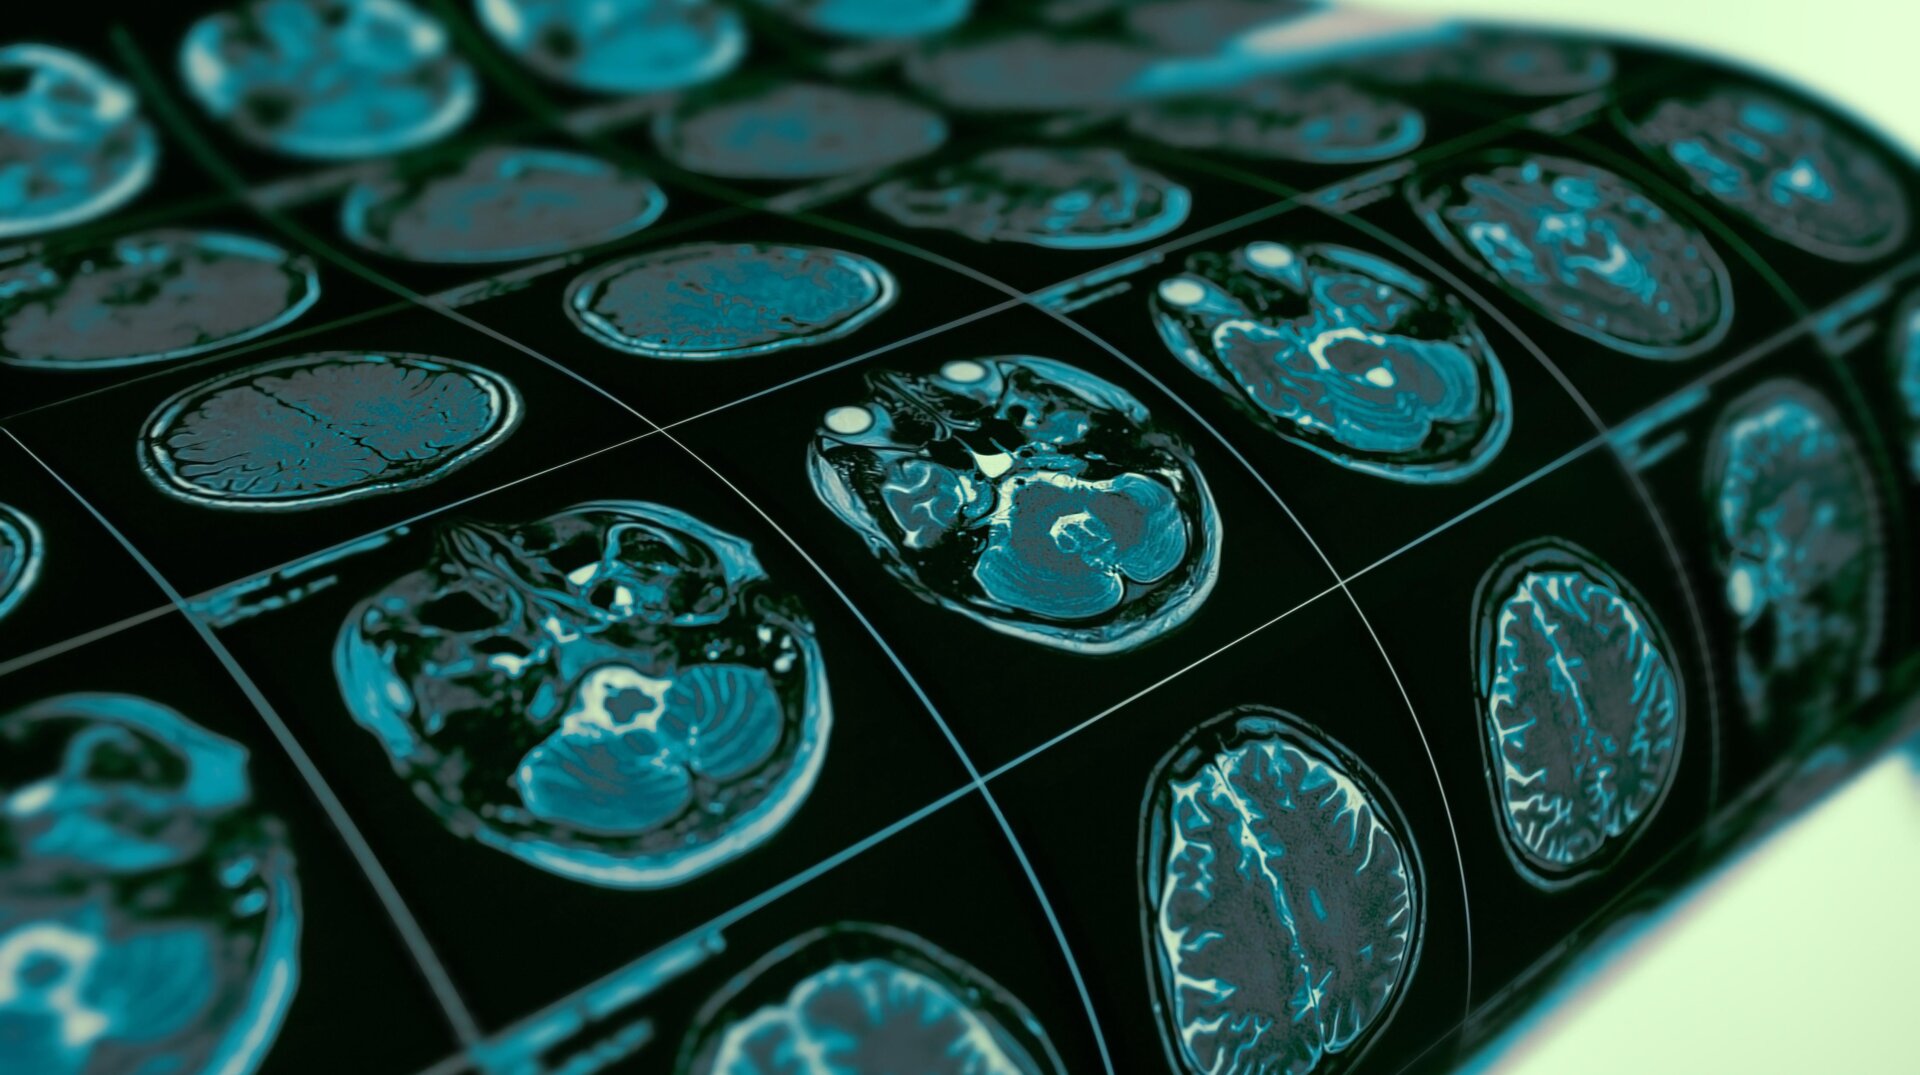

Tiene Prácticamente Garantía De Contraer Alzheimer Si Tiene Esta Variante Genética

Un equipo de científicos parece haber descubierto una causa genética previamente oculta del Alzheimer. En un nuevo estudio realizado el lunes, los investigadores encontraron fuertes evidencia de que las personas que portan dos copias de una variación genética ya ligada al riesgo de Alzheimer están prácticamente destinadas a desarrollar el trastorno neurodegenerativo a medida que avanzan envejecer. Hasta el 2% de la población general puede tener la misma mutación, lo que sugiere que el riesgo genético de Alzheimer es mayor de lo asumido actualmente.

En los datos de NACC, los investigadores encontraron que casi todas las personas con dos APOE4 Los genes mostraron niveles medios a altos de cambios cerebrales asociados con el Alzheimer en el momento de su muerte. A modo de comparación, lo mismo fue sólo verdadero para el 50% de aquellos que APOE3, el más común APOE variante, y que no se cree que afecte el riesgo de Alzheimer. En los datos de biomarcadores, el equipo encontró de manera similar que casi todas las personas con dos APOE4 Las copias tenían niveles anormales de beta amiloide en su líquido espinal (un posible signo temprano de la enfermedad) a los 65 años, mientras que el 75% tenían exploraciones de amiloide positivas. A los 80 años, casi el 90% de estos portadores tenían todos los biomarcadores asociados con amiloide y tau (otro proteína clave para el Alzheimer) que los investigadores pudieron rastrear.

No todas las personas con estos cambios mostrarán síntomas clínicos de Alzheimer antes de morir. Pero los hallazgos, publicado El lunes en la revista Nature Medicine, proporciona una ilustración clara de una penetrancia casi completa, dicen los autores: las probabilidades de que una mutación genética cause un rasgo específico. En este caso, aquellos que tienen dos APOE4 Parece casi seguro que los genes desarrollarán al menos los primeros signos de Alzheimer cuando alcancen los 60 años. Dado ese nivel Sin duda, es más exacto clasificar esta mutación como si representara una “forma genética” distinta del Alzheimer, argumentan los investigadores. tenga en cuenta que se cree que el 2% de la población tiene dos APOE4 copias, lo que haría de esta forma de Alzheimer una de las enfermedades más comunes ligada a un solo gen.